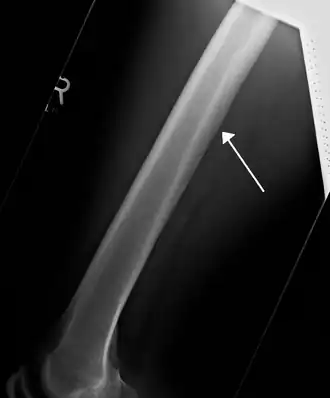

![]() A nutrient artery feeding the femur seen on X-ray | |

The nutrient artery (arteria nutricia, or central artery), usually accompanied by one or two nutrient veins, enters the bone through the nutrient foramen, runs obliquely through the cortex, sends branches upward and downward to the bone marrow, which ramify in the endosteum–the vascular membrane lining the medullary cavity–and give twigs to the adjoining canals. Nutrient arteries are the most apparent blood vessels of the bones.[1]

All bones possess larger or smaller foramina for the entrance of the nourishing blood-vessels; these are known as the nutrient foramina, and are particularly large in the shafts of the larger long bones, where they lead into a nutrient canal, which extends into the medullary cavity (bone marrow cavity).[2]